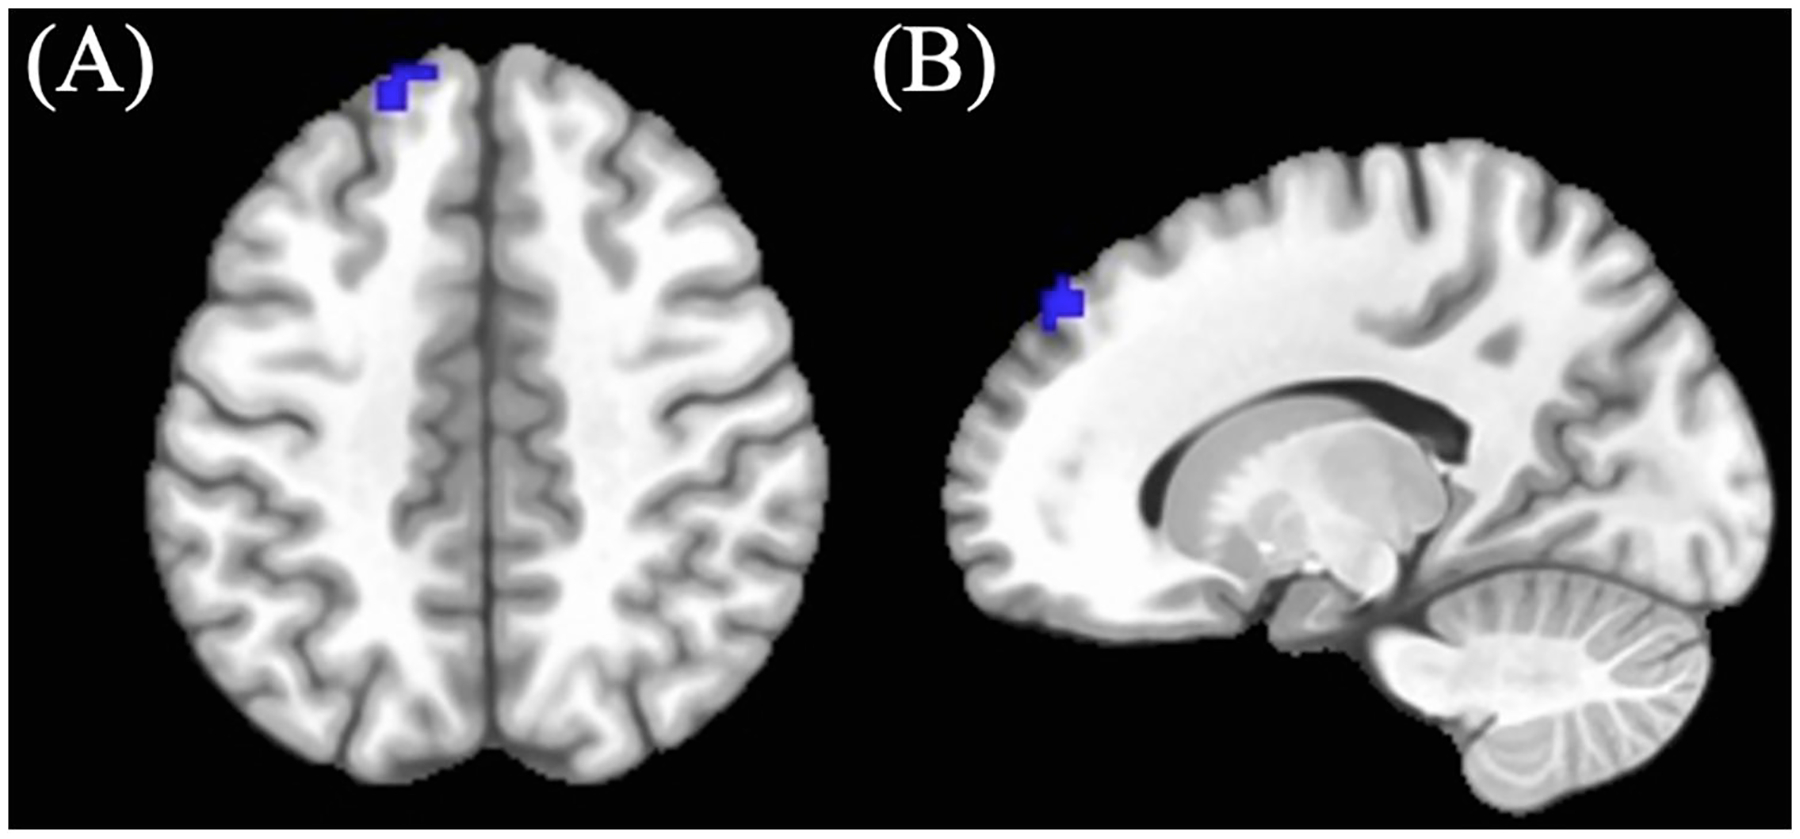

Positive no-go > neutral no-go effects

Cannabis-using participants showed decreased BOLD response (M = −0.25, SD = 0.43) in the left superior frontal region compared to controls in the positive > neutral no-go condition (see Table 3; Figure 2) (controls: M = −0.01, SD = 0.43). (See Table 3).

Decreased left superior frontal and ventral striatum activations were observed in positive response inhibition (i.e., happy No-go) for cannabis-using participants relative to controls. Studies of BOLD activation elicited by inhibitory tasks have shown that cannabis-using groups generally display aberrant BOLD response in frontal regions (ref. 59, ref. 61, ref. 84, ref. 96). In a similar sample, Wallace et al. (ref. 13) found increased activation in left frontal gyrus when examining response inhibition to calm (i.e., neutral) faces. Further, given the mixed findings on BOLD response elicited by positive stimuli (ref. 52, ref. 56, ref. 57), we demonstrate a unique pattern of left superior frontal activation in inhibitory trials with added component of inhibition to positive stimuli. While we do see in non-using teens that more frontal activation is recruited for successful inhibitory response to positive faces (ref. 21, ref. 23), it is hypothesized that cannabis-using participants may not be actively recruiting frontal regions; further evidenced by connectivity studies of reward paradigms, where frontal connectivity network differences are observed even following a period of monitored abstinence (ref. 40, ref. 41). Hypoactivation was observed in positive inhibition trials which additionally aligns with previous MID studies of reward anticipation (ref. 30, ref. 44–ref. 46), however, as this task did not involve “anticipation” per se, these findings may instead represent discrepant BOLD responses elicited by positive inhibition. Findings could be attributed to more effortful inhibition of the ventral striatum when cannabis-using individuals are asked to inhibit response to positive (i.e., rewarding) faces in order to complete the task (relative to the non-using literature 97). Overall, the positive inhibition findings may represent that when cognitive control components are added it could disrupt typical reward processing. Future studies with tasks engaging both inhibition and reward processing are needed as these could present more ecologically valid day-to-day interactions with rewarding stimuli.

The current study found that after at least two-weeks of monitored abstinence, cannabis-using adolescents and young adults displayed increased BOLD response in left middle cingulum and ventral striatum, and decreased BOLD response in left supplemental motor areas in positive Go conditions. In addition, decreased BOLD response in a left superior frontal cluster and ventral striatum in positive No-go conditions was observed in cannabis-using participants. These aberrant BOLD activations align with previous findings and may further implicate compensatory theories within cannabis-using individuals who are recruiting other functional regions to assist in responding to positive stimuli on a Go/No-go task or, may represent increased activation when responding to positive cues and disrupted functional response when an inhibitory control component is added. Ventral striatum outcomes correspond with monetary-incentive investigations (ref. 30), while also representing a novel result in cannabis research relative to the neurodevelopmental adolescent literature on positive affective processing (ref. 23). Further, we did not observe significant context-dependent connectivity differences between the ventral striatum and other cortical regions (ref. 15). Overall, these findings, coupled with the existing literature, suggest that BOLD activity elicited by either engagement or inhibition to positive faces—even following at least two-weeks of monitored abstinence—differs between cannabis-using and non-using adolescents and young adults. Jointly investigating response inhibition and reward processing in cannabis-using individuals may present more ecologically valid methods of examining contributions to escalation or continuation of use into adulthood, as this interplay is described within withdrawal stages of addiction models (ref. 33, ref. 47). Future prospective, longitudinal studies, are needed to further elucidate the causal relationship between escalating cannabis use and functional activation elicited by positive stimuli, specifically examining the contributions of the ventral striatum in this relationship.